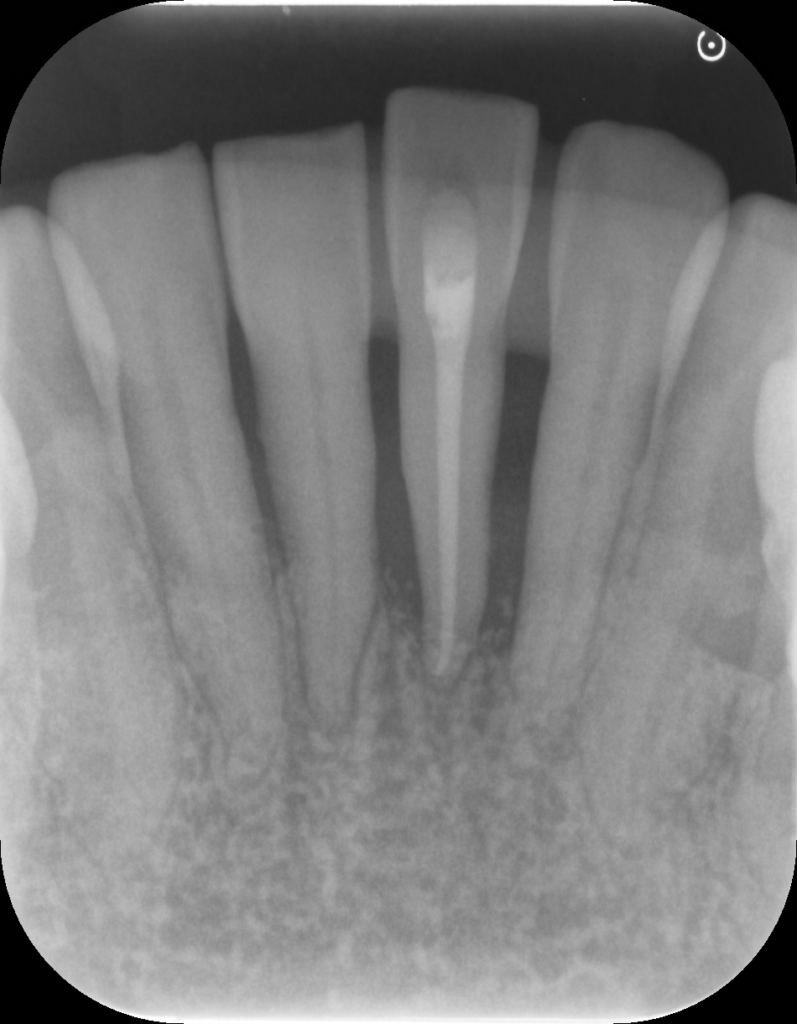

↑治療前後で骨の状態が改善しています。現在は隣の歯と固定して経過を見ています。

↑レントゲンで骨吸収を認めます。歯肉を切開すると実際に骨がありません。